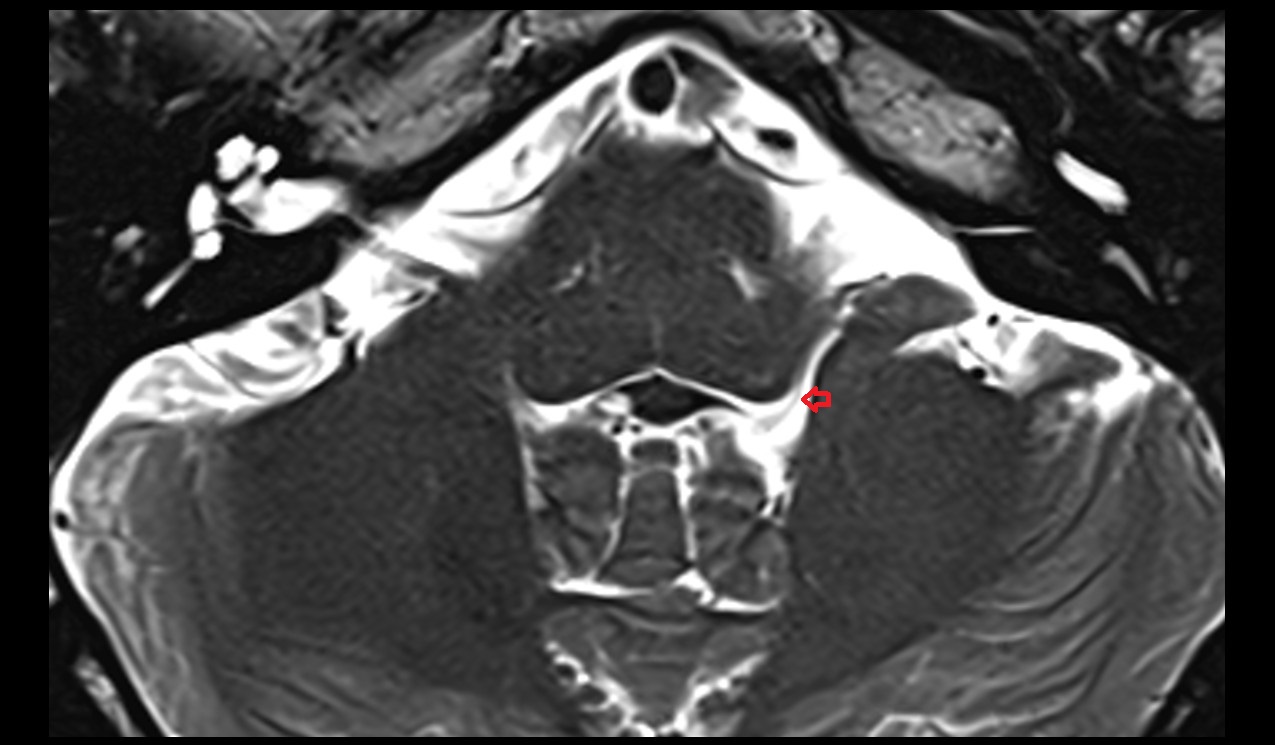

- Lateral aperture of fourth ventricle (foramen of Luschka)